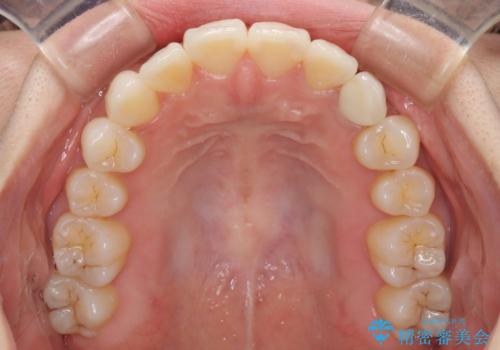

- 前歯のデコボコと残っている乳歯の部分へのインプラント治療を希望して来院された患者様です。

当初は目立たない上下裏側矯正を希望されていましたが、歯並びの悪さによる磨き残しが多く、歯肉炎が認められたため、より清潔な環境で治療を進められるインビザラインを選択することとしました。

前歯のデコボコが強かったため、上の奥歯を後方に動かす量が多くなり、結果として2年以上の治療期間を擁することとなりました。

歯並びが整ったことで治療前に認められた歯肉炎は全くなくなり、患者様には大変満足していただきました。